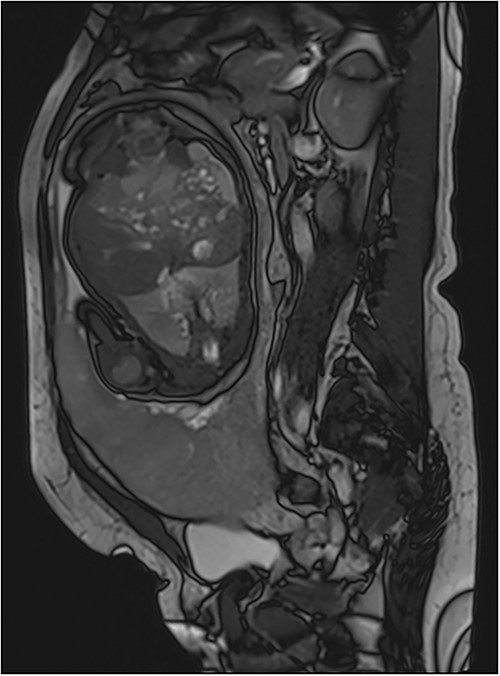

Her MRI showed some thick linear and round bands arising from the maternal side of the placenta seen in low signal in single-shot fast spin echo (SSFSE) T2-Weighted images (HASTE) and in high signal on Balanced Steady State Free Precession (bSSFP) (True Fisp), corresponding to dark intra-placental bands (Fig. 2). The most important finding was myometrial thinning and the bulging of the placenta within the Cesarean scar as well discontinuity in the urinary bladder wall with its invasion by the placental tissue (Fig. 2). These abnormalities were associated to some tortuous bands in a signal on all sequences corresponding to vessels. The diagnosis of placenta percreta was then made and the patient was referred to the obstetrics department for urgent care.

(a)–(d) Sagittal sequences showing dark intra-placental bands (arrows) in low signal in HASTE sequences and in high signal on truFISP. (e) Sagittal HASTE and (f) coronal truFISP sequences showing myometrial thickening and discontinuity in the bladder wall as well as its invasion by the placental tissue (arrow).